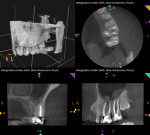

This patient's reported history of cold sensitivity, current symptoms (including their localization), and ability to achieve partial symptom alleviation with ibuprofen were suggestive of the development of a pulpal pathosis in the mandibular left quadrant; therefore, the objective examination was guided to explore this possibility. The clinical examination revealed intact restorations and normal periodontal findings. To replicate the patient's symptoms, pulp sensitivity tests and periodontal ligament tests were performed. Teeth Nos. 18, 19, and 20 were similarly tender to percussion, palpation, and biting. During cold testing, teeth Nos. 18, 20, and 21, exhibited normal responses; however, tooth No. 19 failed to exhibit a response. No clinical abnormalities were noted in the upper left quadrant. CBCT imaging was performed, which revealed widening in the apical region of the periodontal ligament of tooth No. 19 only (Figure 2).

Given the findings of the clinical and radiographic examinations, the diagnosis and suspected source of pain was pulpal necrosis with symptomatic apical periodontitis associated with tooth No. 19.5 The completion of root canal therapy for tooth No. 19 (Figure 3) resulted in resolution of the patient's symptoms, and her physician tapered her off of the carbamazepine without complication.

The information obtained from the subjective examination was used to guide the in-office objective examination. First, a comprehensive clinical examination was performed, which revealed well-adapted, full-coverage porcelain-fused-to-metal crowns on teeth Nos. 14 and 15, the partial eruption of teeth Nos. 16 and 17, and large amalgam buildups with stained margins on teeth Nos. 18 and 19. Gingival irritation was evident surrounding teeth Nos. 16 and 17. Next, sensitivity tests were performed. None of the teeth in the upper or lower left quadrants were sensitive to percussion, palpation, or biting; however, teeth Nos. 12, 13, 16, 17, 18, 20, and 21 responded normally to cold and electric pulp testing, whereas teeth Nos. 14, 15, and 19 were nonresponsive to both. CBCT imaging revealed evidence of a periapical pathosis on the mesiobuccal root of tooth No. 14, which was related to an untreated second mesiobuccal canal (Figure 4). In addition, maxillary sinus mucositis was present adjacent to tooth No. 14, and between teeth Nos. 15 and 16. Tooth No. 19 also demonstrated evidence of a developing apical pathosis (Figure 5).

The diagnosis for tooth No. 14 was previously treated with asymptomatic apical periodontitis. Tooth No. 19, however, was confirmed to have pulpal necrosis with asymptomatic apical periodontitis.5 These findings indicated that tooth No. 19 was the source of patient's pain given the recent nature of pulpal degeneration. Nonsurgical root canal therapy was performed on tooth No. 19, which resulted in resolution of the reported pain (Figure 6). Regarding tooth No. 14, plans were made to perform nonsurgical root canal retreatment following lifting of the COVID-19-related dental practice restrictions.